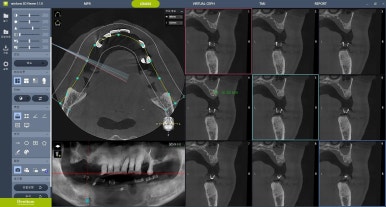

3D CT와 구강 스캐너를 이용해

잇몸뼈의 위치와 각도를 정밀하게 분석하고...

컴퓨터 시뮬레이션을 통해

미리 수술 경로를 계획하기 때문에...

잇몸을 크게 열지 않고도

정확하게 임플란트를 심을 수 있게 됩니다.